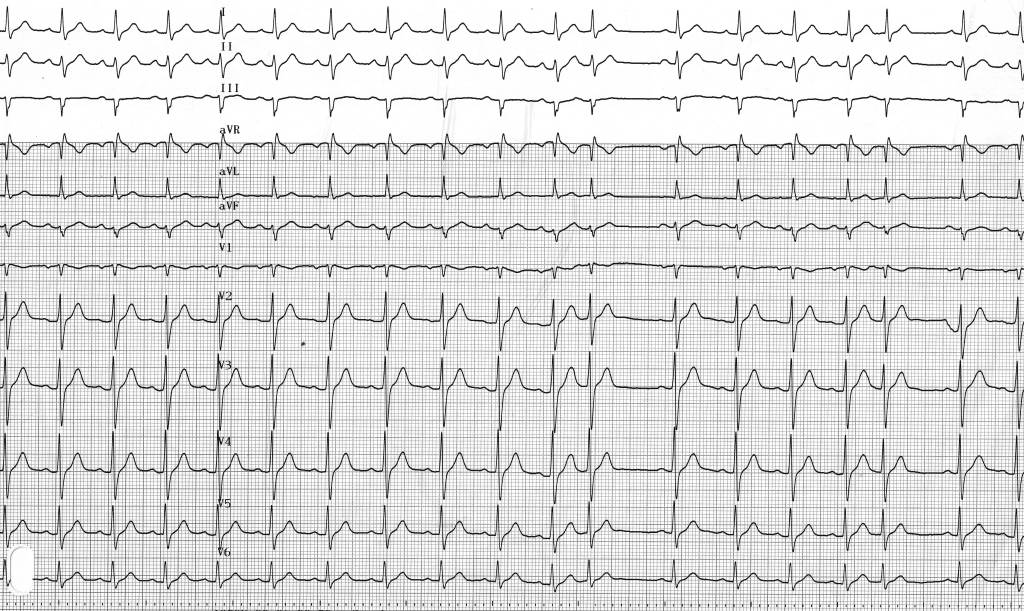

Une extrasystole atriale peut survenir comme sur ce tracé durant la repolarisation ventriculaire (sur l’onde T suivant le complexe QRS précédent). L’électrocardiogramme de surface enregistre au niveau de la peau, l’intégralité des potentiels générés par le coeur. En raison d’une masse plus faible, l’amplitude des signaux générés par l’oreillette est beaucoup plus faible que celle des signaux générés par le ventricule (complexe QRS ou onde T). De surcroit, la pente (“molle”) de ces 2 signaux (onde P et onde T) est relativement similaire et significativement différente par rapport à celle d’un QRS (pente plus aiguë). Le diagnostic d’extrasystole atriale peut donc parfois être difficile et une analyse minutieuse de toutes les dérivations est nécessaire.

Un mécanisme focal des arythmies atriales a été montré dans l’initiation d’un nombre important d’épisodes de FA. En effet, le type d’extrasystole atriale observée sur ce tracé, avec un aspect caractéristique P/T et provenant pour majorité de l’ostium des veines pulmonaires, représente la gâchette initiatrice nécessaire à l’induction d’épisodes d’arythmie atriale. L’implication thérapeutique est directe car ces extrasystoles sont accessibles à un traitement radical par ablation (déconnexion des veines pulmonaires). Il convient donc d’identifier ce type d’extrasystoles “cachées” dans l’onde T et de les différencier des extrasystoles jonctionnelles qui représentent le diagnostic différentiel pour un battement prématuré avec QRS fin.